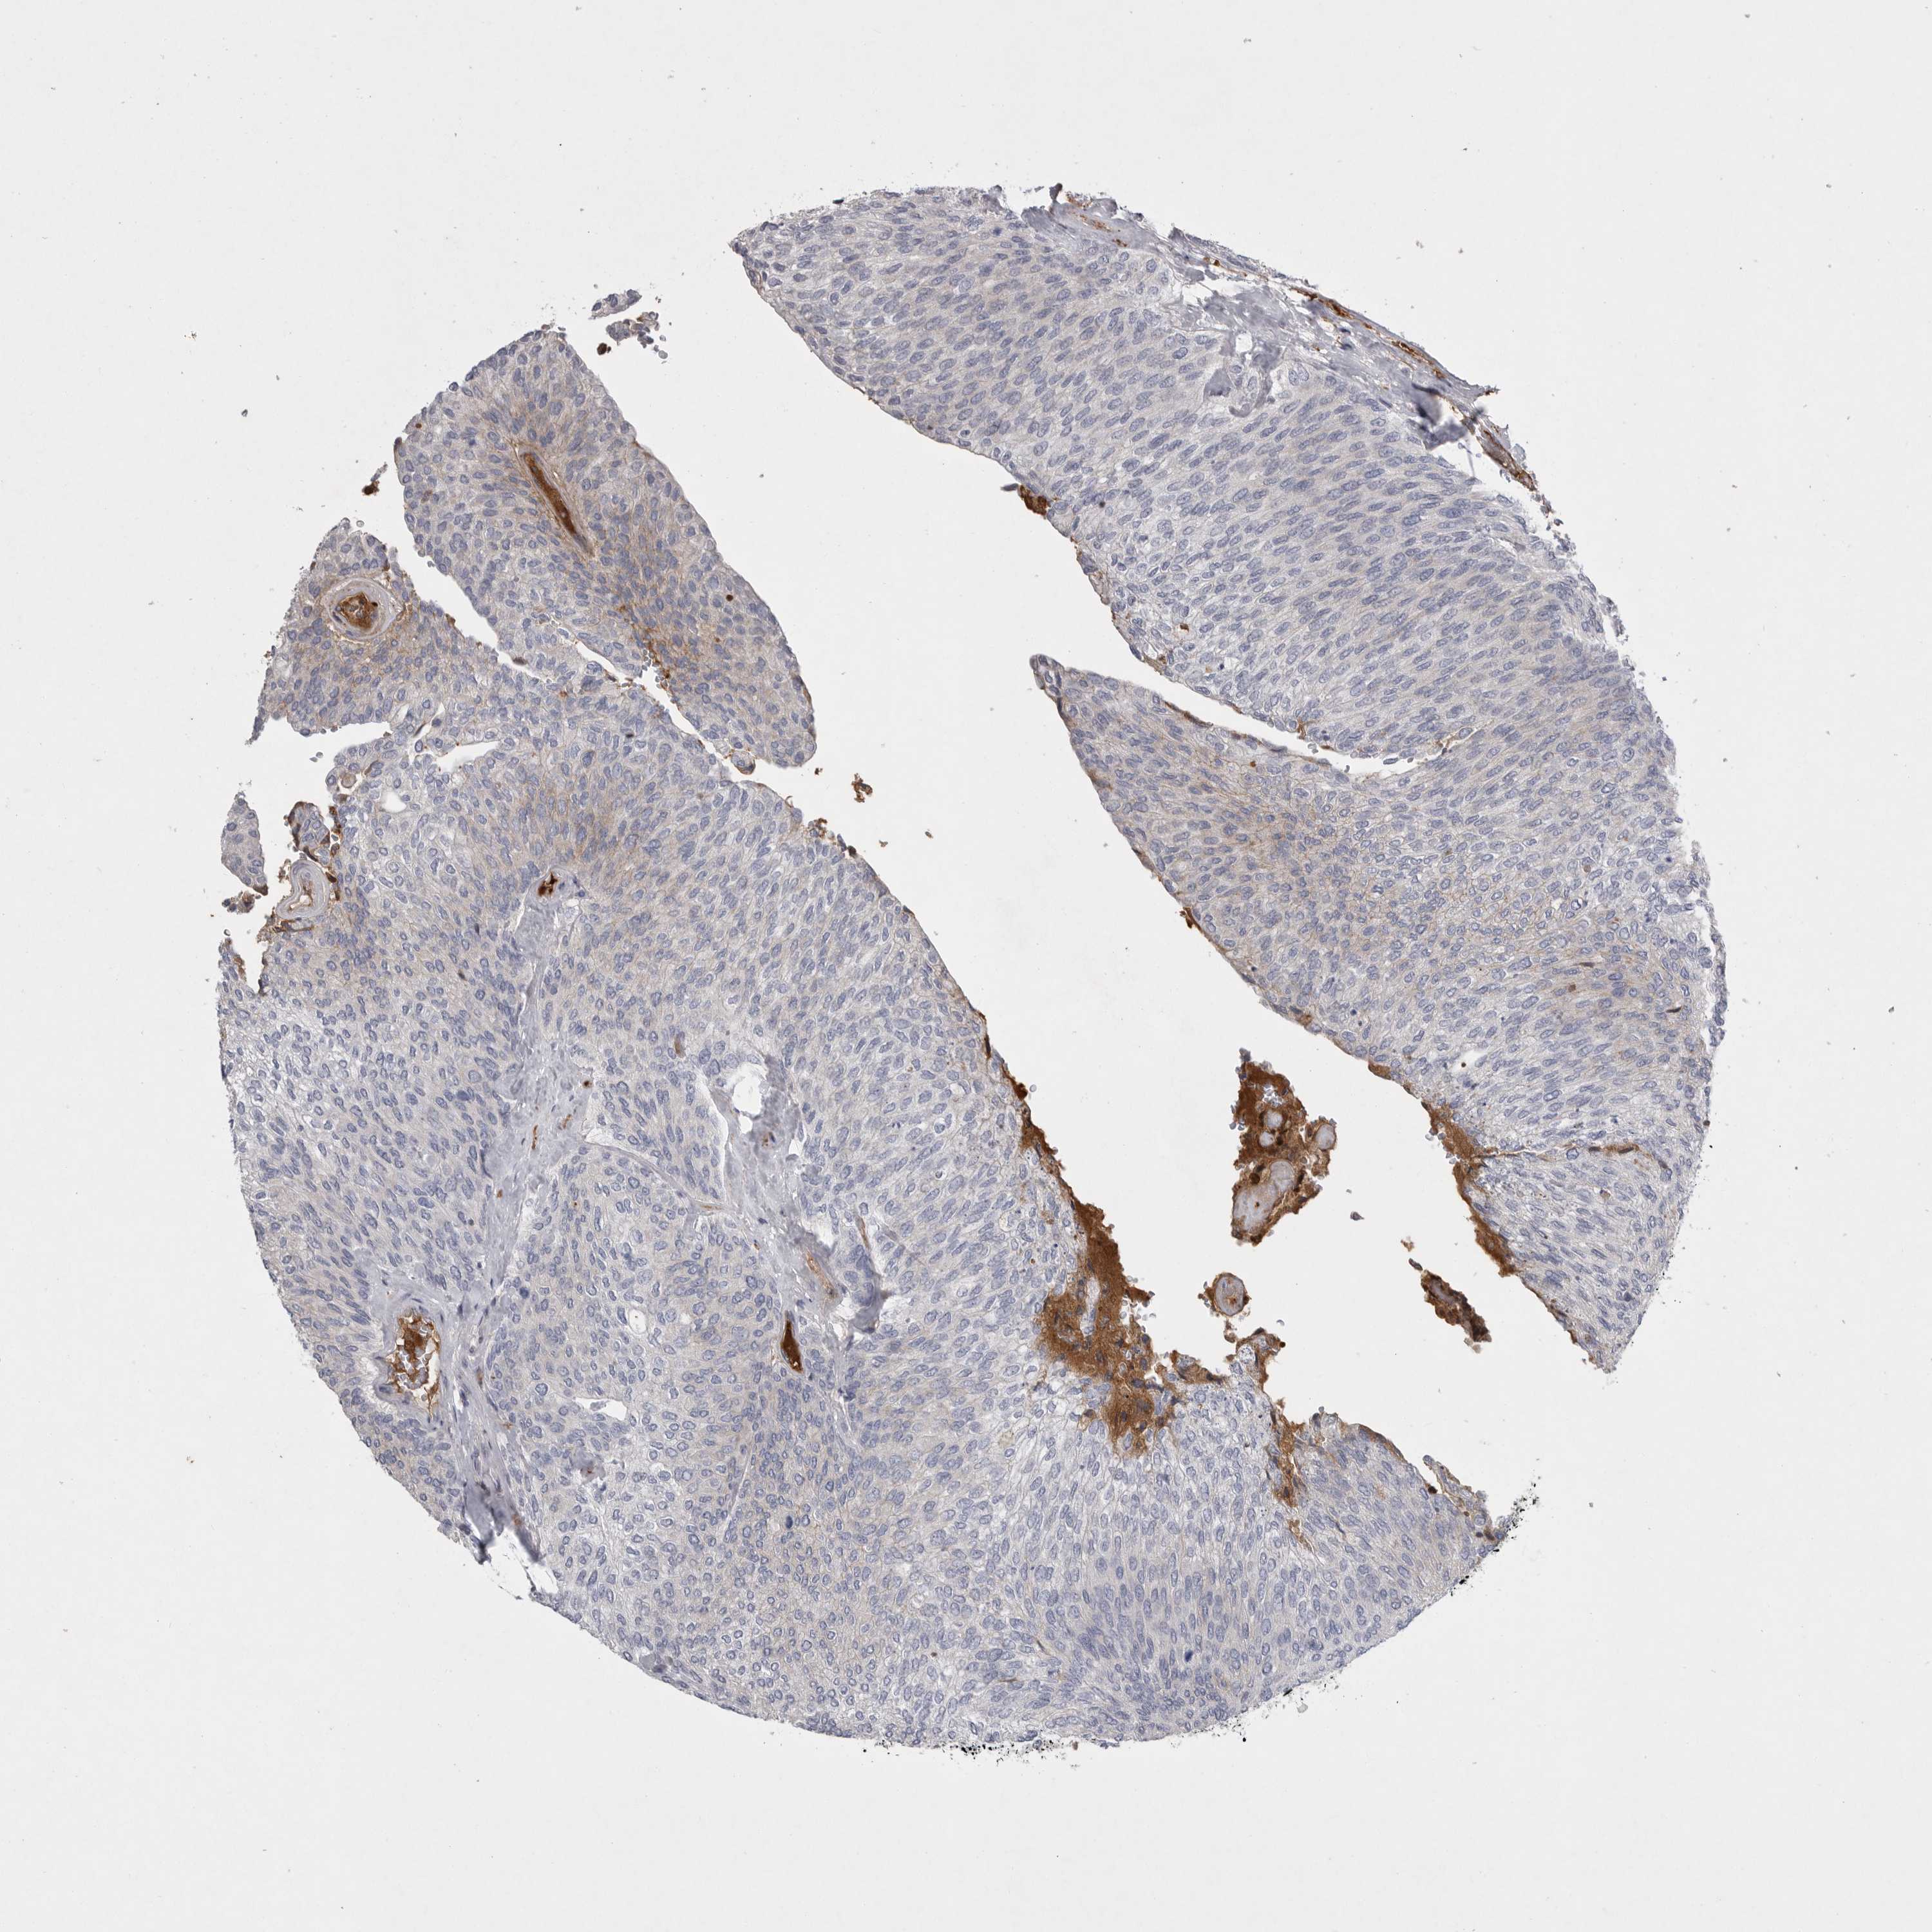

UROTHELIAL CANCER - Protein expressioni

A mouse-over function shows sample information and annotation data. Click on an image to view it in a full screen mode. Samples can be filtered based on level of antibody staining by selecting one or several of the following categories: high, medium, low and not detected. The assay and annotation is described here.

Note that samples used for immunohistochemistry by the Human Protein Atlas do not correspond to samples in the TCGA dataset.

Antibody stainingi

Antibody staining in the annotated cell types in the current human tissue is reported as not detected, low, medium, or high, based on conventional immunohistochemistry profiling in selected tissues. This score is based on the combination of the staining intensity and fraction of stained cells.

Each image is clickable and will lead to virtual microscopy that enables deeper exploration of all samples and also displays staining intensity scores, fraction scores and subcellular localization as well as patient and tissue information for each sample.

Antibody HPA027367

Antibody HPA027396

Antibody CAB005036

Staining

High

Medium

Low

Not detected

Intensity

Strong

Moderate

Weak

Negative

Quantity

>75%

75%-25%

<25%

None

Location

Nuclear

Cytoplasmic/membranous

Cytoplasmic/membranous,nuclear

Urothelial carcinoma, Low grade

Urothelial carcinoma, High grade